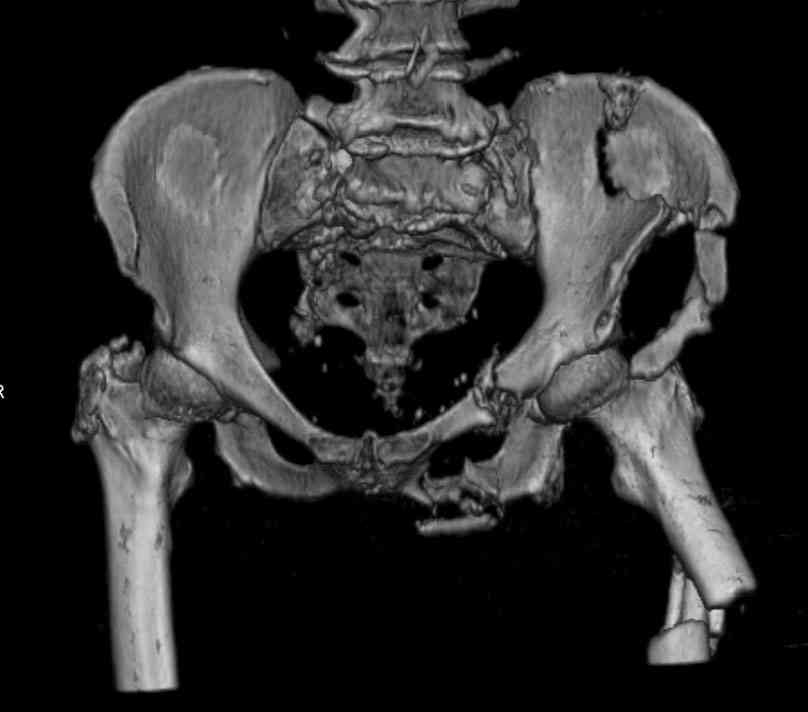

Уважаемые коллеги, в продолжение обсуждения перелома костей таза с отрывами остей досылаю R-снимки (КТ и КТ с 3d реконструкцией)